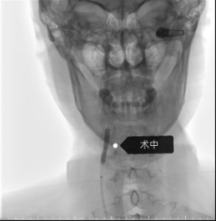

手术当日,神经内科介入团队娴熟操作介入设备,导丝、导管、支架系统操作顺利送达指定部位,成功将支架输送至狭窄部位并精准释放,瞬间打通了狭窄严重的血管,恢复了大脑的正常供血,整台手术流畅顺利,采用局部麻醉,患者全程清醒,无身体不适反应。

术后患者便可下床上厕所,行动自如,日常活动恢复正常,术前症状消失,脸上露出了久违的笑容。对于如此迅速的重获健康,患者及家属激动不已,特意将两面满载感激之情的锦旗送到科室,盛赞神经内科团队“医德高尚,仁心仁术”。